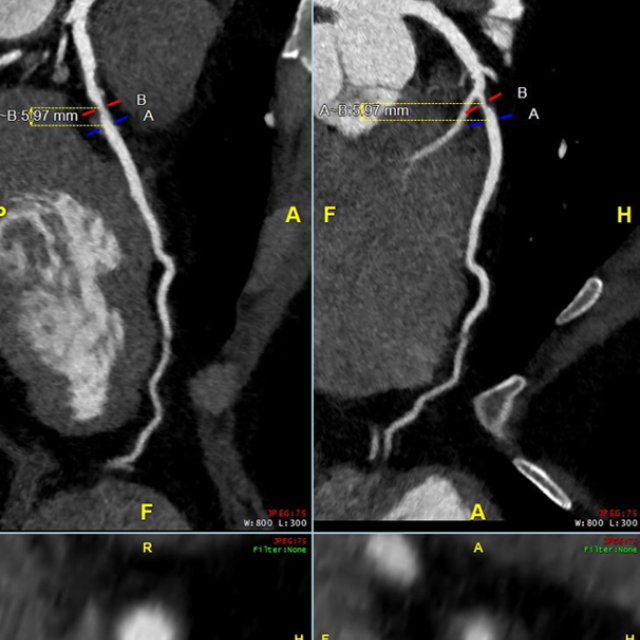

Beginning in 2026, interventional cardiology fellows will be offered formal training in coronary CTA, relying on structured CT reading sessions, lectures, and imaging case files to achieve Level II cardiac CT proficiency and qualification for the cardiac CT boards upon completion of interventional training. As our field shifts away from traditional stress imaging and towards coronary CTA as the preferred non-invasive method of assessment of CAD, there are emerging needs for interventional cardiologists to master coronary CTA for anatomic assessment of CAD, physiologic assessment with FFRCT and myocardium at-risk, morphologic assessment of plaque burden and characterization, and advanced planning of PCI for calcified plaque, bifurcation lesions, and CTO. Since ad-hoc PCI has become embedded in interventional practice, PCI planning with CTA allows precise equipment selection; reduces procedural time and radiation exposure to the patient and staff; allows the best opportunity for risk assessment for the patient and family, even before the patient goes to the cardiac catheterization laboratory. The Interventional Cardiology Fellowship Program at William Beaumont University Hospital is the first to offer formal cardiac CT training as part of its curriculum.